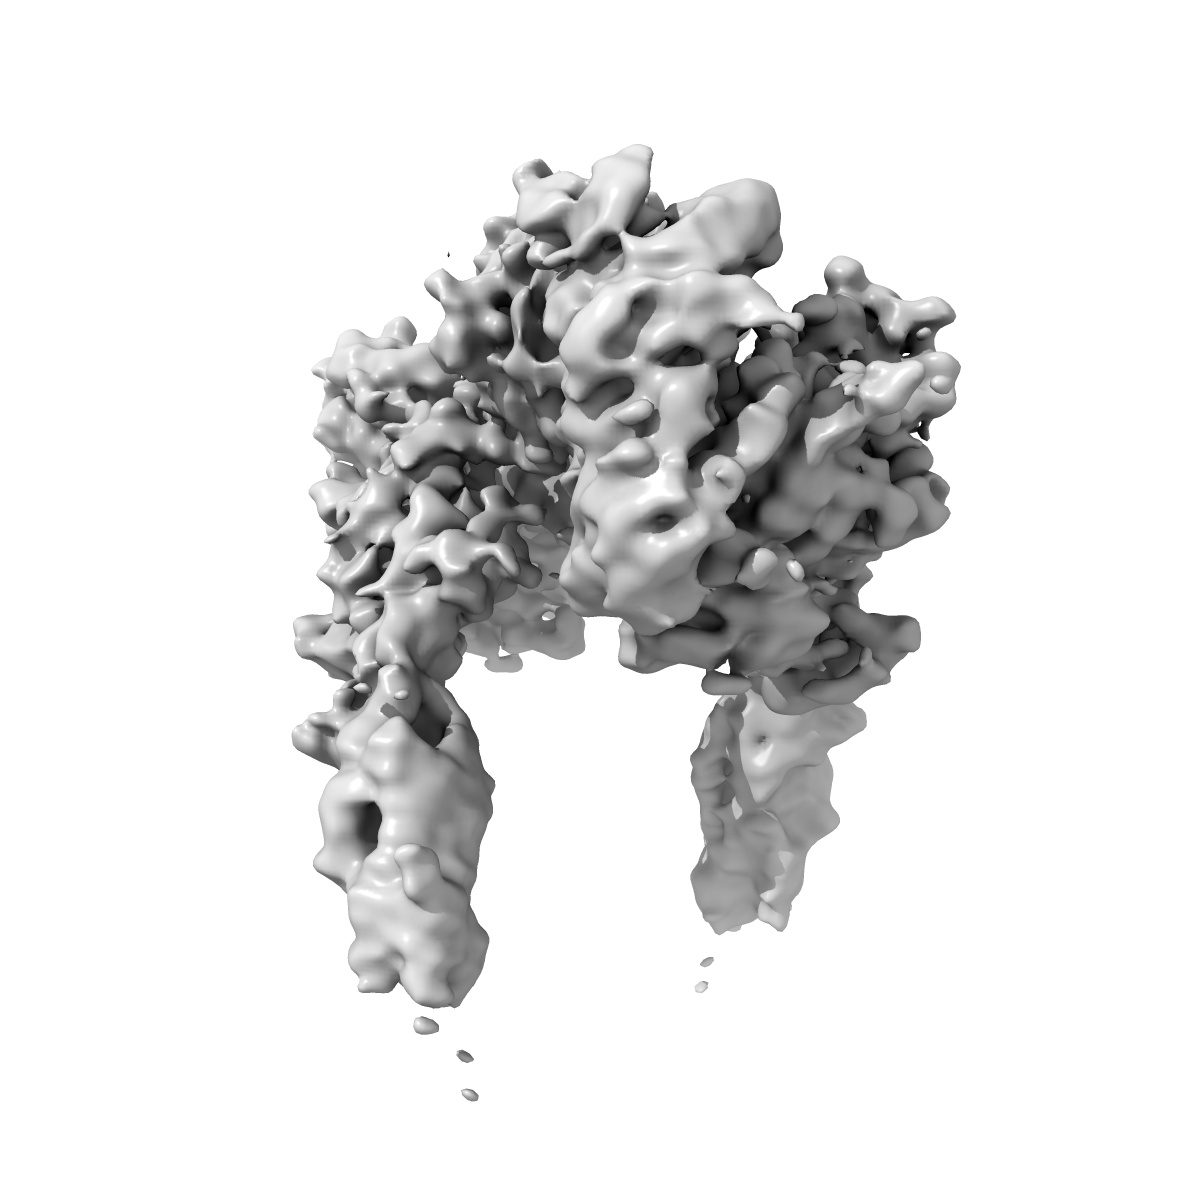

Cryo-EM structure of the IR/IGF-I complex, conformation 2

Sample: The complex of human IR with 4 IGF-I

Fitted models: 8x2m